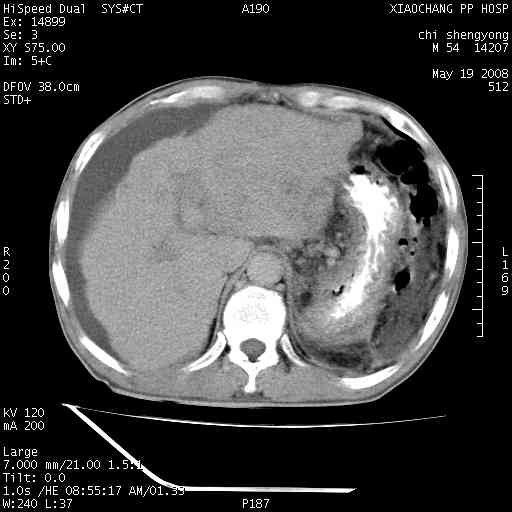

以下是引用zjzjr在2008-5-21 10:52:00的发言:[br]肝左叶巨块型肝癌伴门静脉左支瘤栓形成.肝硬化、腹水,胃底静脉曲张,脾术后改变。

以下是引用随光逐影在2008-5-21 16:20:00的发言:[br]1)肝左叶肝癌伴门静脉左支瘤栓形成,腹膜后淋巴结转移。2)肝硬化、腹水、胃底静脉曲张。3)胆囊炎。4)脾脏缺如,为切除术后所致。